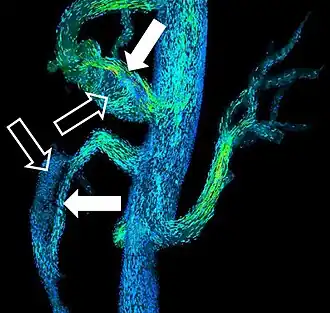

MRI diffusion tensor imaging of white matter tracts

MRI is the investigative tool of choice for neurological cancers over CT, as it offers better visualization of the posterior cranial fossa, containing the brainstem and the cerebellum. The contrast provided between grey and white matter makes MRI the best choice for many conditions of the central nervous system, including demyelinating diseases, dementia, cerebrovascular disease, infectious diseases, Alzheimer's disease and epilepsy.[22][23][24] Since many images are taken milliseconds apart, it shows how the brain responds to different stimuli, enabling researchers to study both the functional and structural brain abnormalities in psychological disorders.[25] MRI also is used in guided stereotactic surgery and radiosurgery for treatment of intracranial tumors, arteriovenous malformations, and other surgically treatable conditions using a device known as the N-localizer.[26][27][28] New Artificial intelligence in healthcare tools have demonstrated higher image quality and morphometric analysis in neuroimaging with the application of a denoising system.[29]

Diffusion tensor DTI Mainly tractography (pictured) by an overall greater Brownian motion of water molecules in the directions of nerve fibers.[70]

• Evaluating white matter deformation by tumors[70]

• Reduced fractional anisotropy may indicate dementia.[71]